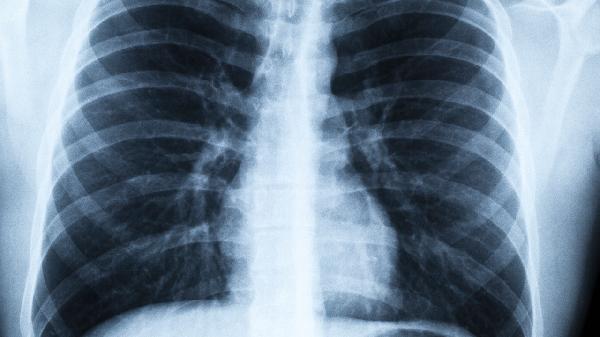

2、影像学检查

颈部CT能清晰显示纵隔淋巴结状况,低剂量螺旋CT对早期肺癌检出率比胸片高6倍。